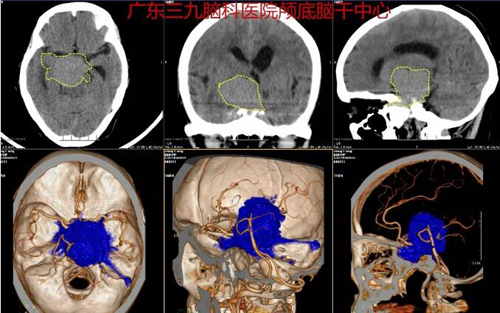

图1:术前CTA示右侧岩斜区占位性病变内存在多发小血管,考虑为脑膜瘤可能,邻近双侧颈内动脉、基地动脉及右侧大脑后动脉明显受推挤。

图3:术后CT示右侧岩斜区术后改变,右侧岩斜区占位性病变已切除。